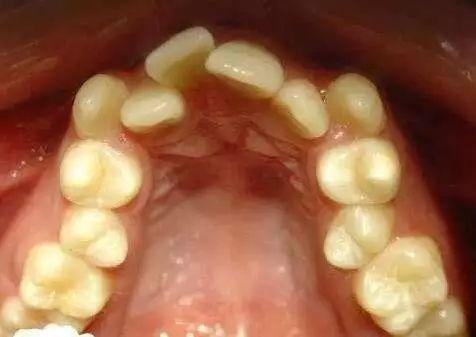

年纪轻轻就咀嚼不力? 这个隐患有可能让你青年失牙!

在你长期不注重口腔清洁之后,在你无数次用牙齿咬开啤酒盖之后,在你不小心磕到牙齿之后,猛然地发现自己牙齿居然不得劲儿了,心想如此年纪轻轻就松动,难道要未老先衰吗?

牙齿松动是牙齿不健康的表现,一旦发现一定要及时就医,否则最终会导致牙齿脱落,很有可能面临青年失牙、中年失牙,影响工作与生活。